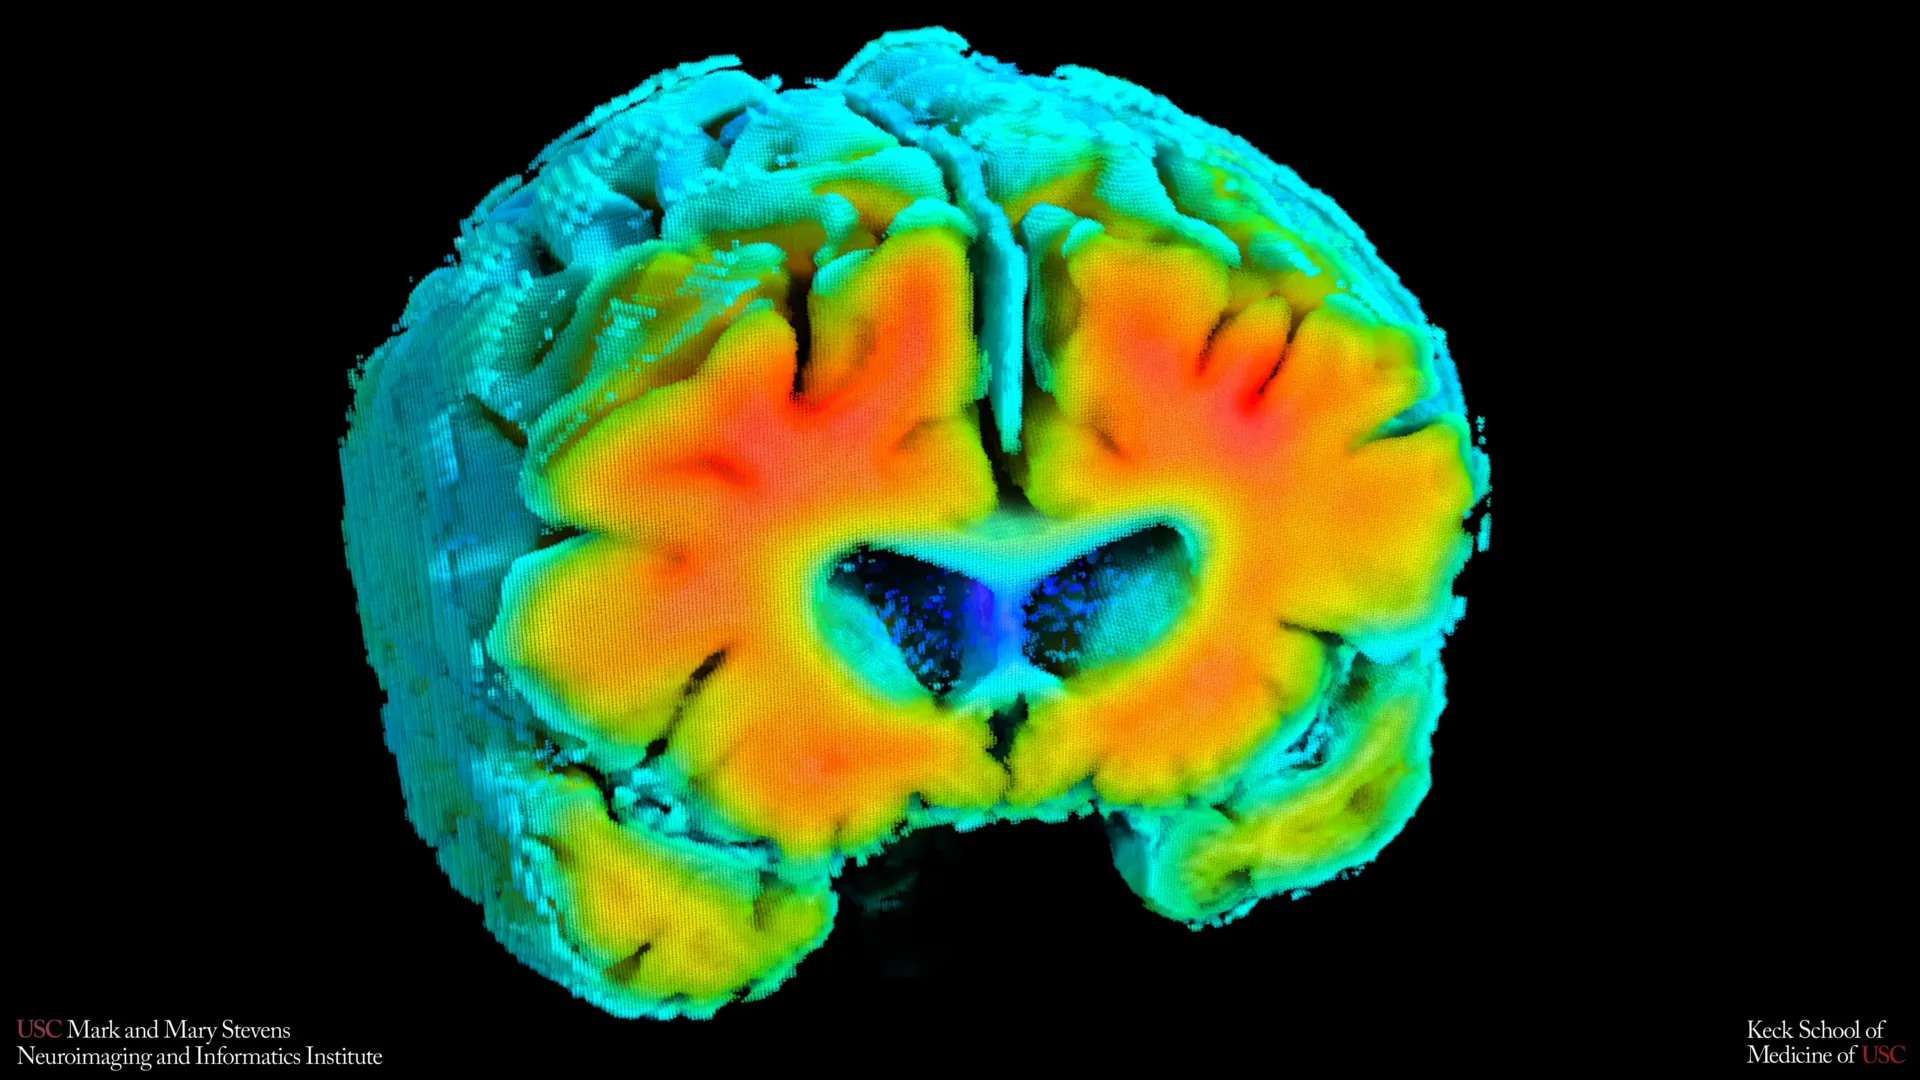

New investigations spearheaded by the Mark and Mary Stevens Neuroimaging and Informatics Institute (Stevens INI) at the Keck School of Medicine of USC suggest a profound connection between subtle alterations in the brain’s circulatory system and the nascent stages of Alzheimer’s disease. This groundbreaking research, published in the esteemed journal Alzheimer’s and Dementia: The Journal of the Alzheimer’s Association, postulates that the efficiency with which blood navigates the brain and the subsequent oxygenation of neural tissues may serve as an early, non-invasive marker for individuals at risk of developing this debilitating neurodegenerative condition.

To precisely quantify these intricate circulatory dynamics, the research team employed two sophisticated yet entirely painless diagnostic modalities. Transcranial Doppler (TCD) ultrasound was utilized to precisely measure the velocity of blood flow through the brain’s principal arterial pathways, offering a quantitative assessment of cerebral perfusion. Concurrently, near-infrared spectroscopy (NIRS) was employed to gauge the efficacy of oxygen diffusion from the blood into the cortical tissues located near the surface of the brain. These non-invasive approaches allowed for a detailed, real-time evaluation of the brain’s vascular performance without imposing any discomfort or risk upon the participants.

Following the acquisition of raw data from these instruments, the researchers applied advanced mathematical algorithms and computational modeling. This sophisticated analysis integrated the individual readings from TCD and NIRS into composite indicators of cerebrovascular function. These synthesized metrics provided a holistic picture of how effectively the brain’s circulatory system adapted to subtle physiological changes, reflecting its dynamic capacity to maintain optimal perfusion and oxygenation under varying conditions.

Dr. Meredith N. Braskie, the senior author of the research and an assistant professor of neurology at Keck School of Medicine, commented on the significance of these vascular measures. "These vascular assessments are capturing a vital aspect of brain health," she explained. "They appear to align remarkably well with the findings obtained from magnetic resonance imaging (MRI) and positron emission tomography (PET) scans, which are the standard tools for investigating Alzheimer’s disease. This provides invaluable insights into the intricate relationship between vascular integrity and established biomarkers of Alzheimer’s risk."